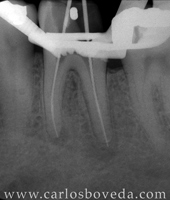

Retratamiento de Conductos en Una Sesión - (formato Quicktime)